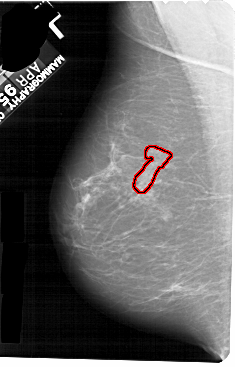

A_1273_1.RIGHT_CC

RIGHT_CC LINES 5491 PIXELS_PER_LINE 3091 BITS_PER_PIXEL 12 RESOLUTION 43.5 NON_OVERLAY

FILE: A_1273_1.LEFT_CC.OVERLAY

TOTAL_ABNORMALITIES 1

ABNORMALITY 1

LESION_TYPE CALCIFICATION TYPE PUNCTATE DISTRIBUTION SEGMENTAL

ASSESSMENT 4

SUBTLETY 1

PATHOLOGY BENIGN

TOTAL_OUTLINES 1

BOUNDARY